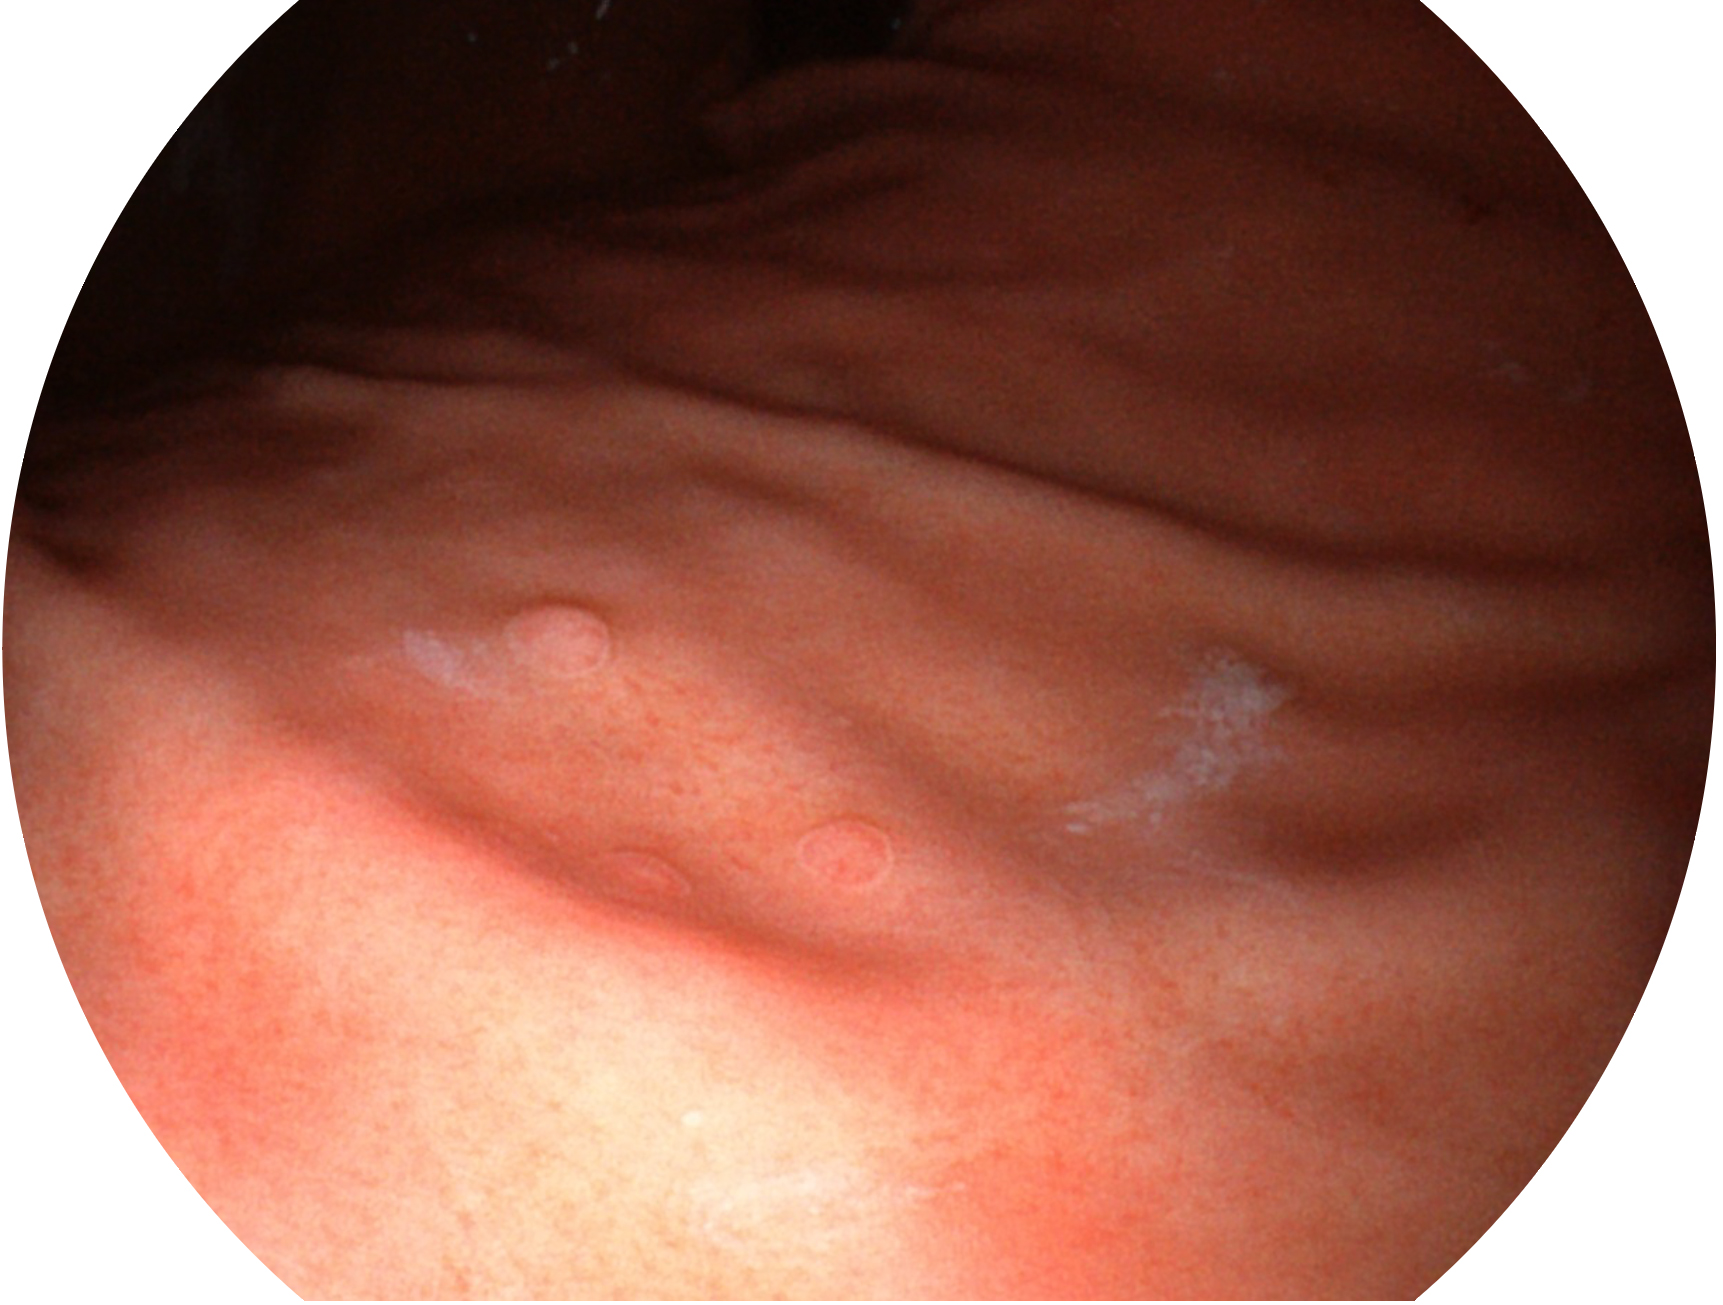

百老汇电子游戏官网新开发的内镜染色技术,主要是基于多波长LED 光源的开发,VLS-55Q 四波长LED 光源是由四个不同颜色的LED光按照相应照明模式所规定的特定发光比例进行合束后形成,合束后形成的照明光的光谱由红光、绿光、蓝光及蓝紫光这四个不同的波段范围构成。具有更高光谱自由度,通过光谱比例的控制,实现了聚谱成像技术,英文全称为“Spectral Focused Imaging, SFI”,缩写为“SFI”和光电复合染色成像技术,英文全称为“Versatile Intelligent Staining Technology, VIST”,缩写为“VIST”。